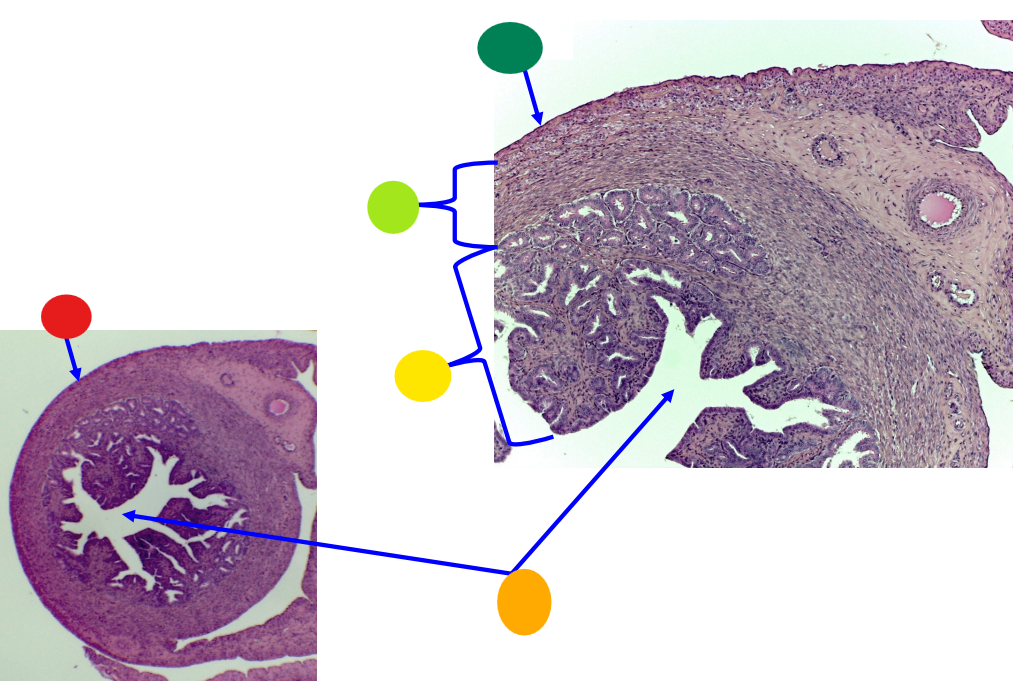

red

primary oocyte

orange

zona pellucida

yellow

granulosa cells

light green

developing thecal cells

What is this

secondary follicle

red

granulosa cells

orange

primary or secondary oocyte

yellow

oocyte nucleus

light green

zona pellucida

dark green

cumulus oophorus

light blue

antrum

dark blue

thecal cells

what is this

tertiary follicle